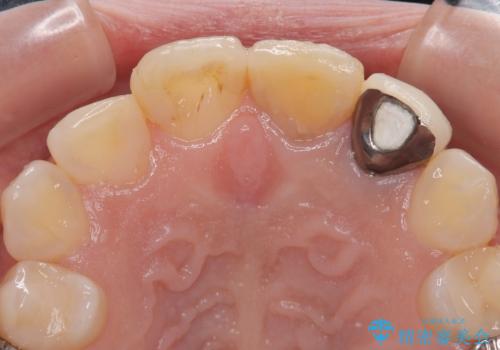

2本とも歯の神経が取り除かれており、真ん中の歯は徐々に歯の色が茶色くなってきており、隣の歯は保険診療で装着したプラスチックのクラウンが徐々に黄ばんできている状態でした。

両歯とも根尖部付近を歯肉から触れると痛みを感じており、3次元CTを撮影したところ、前から2番目の歯の根尖部に病変があることが分かりました。